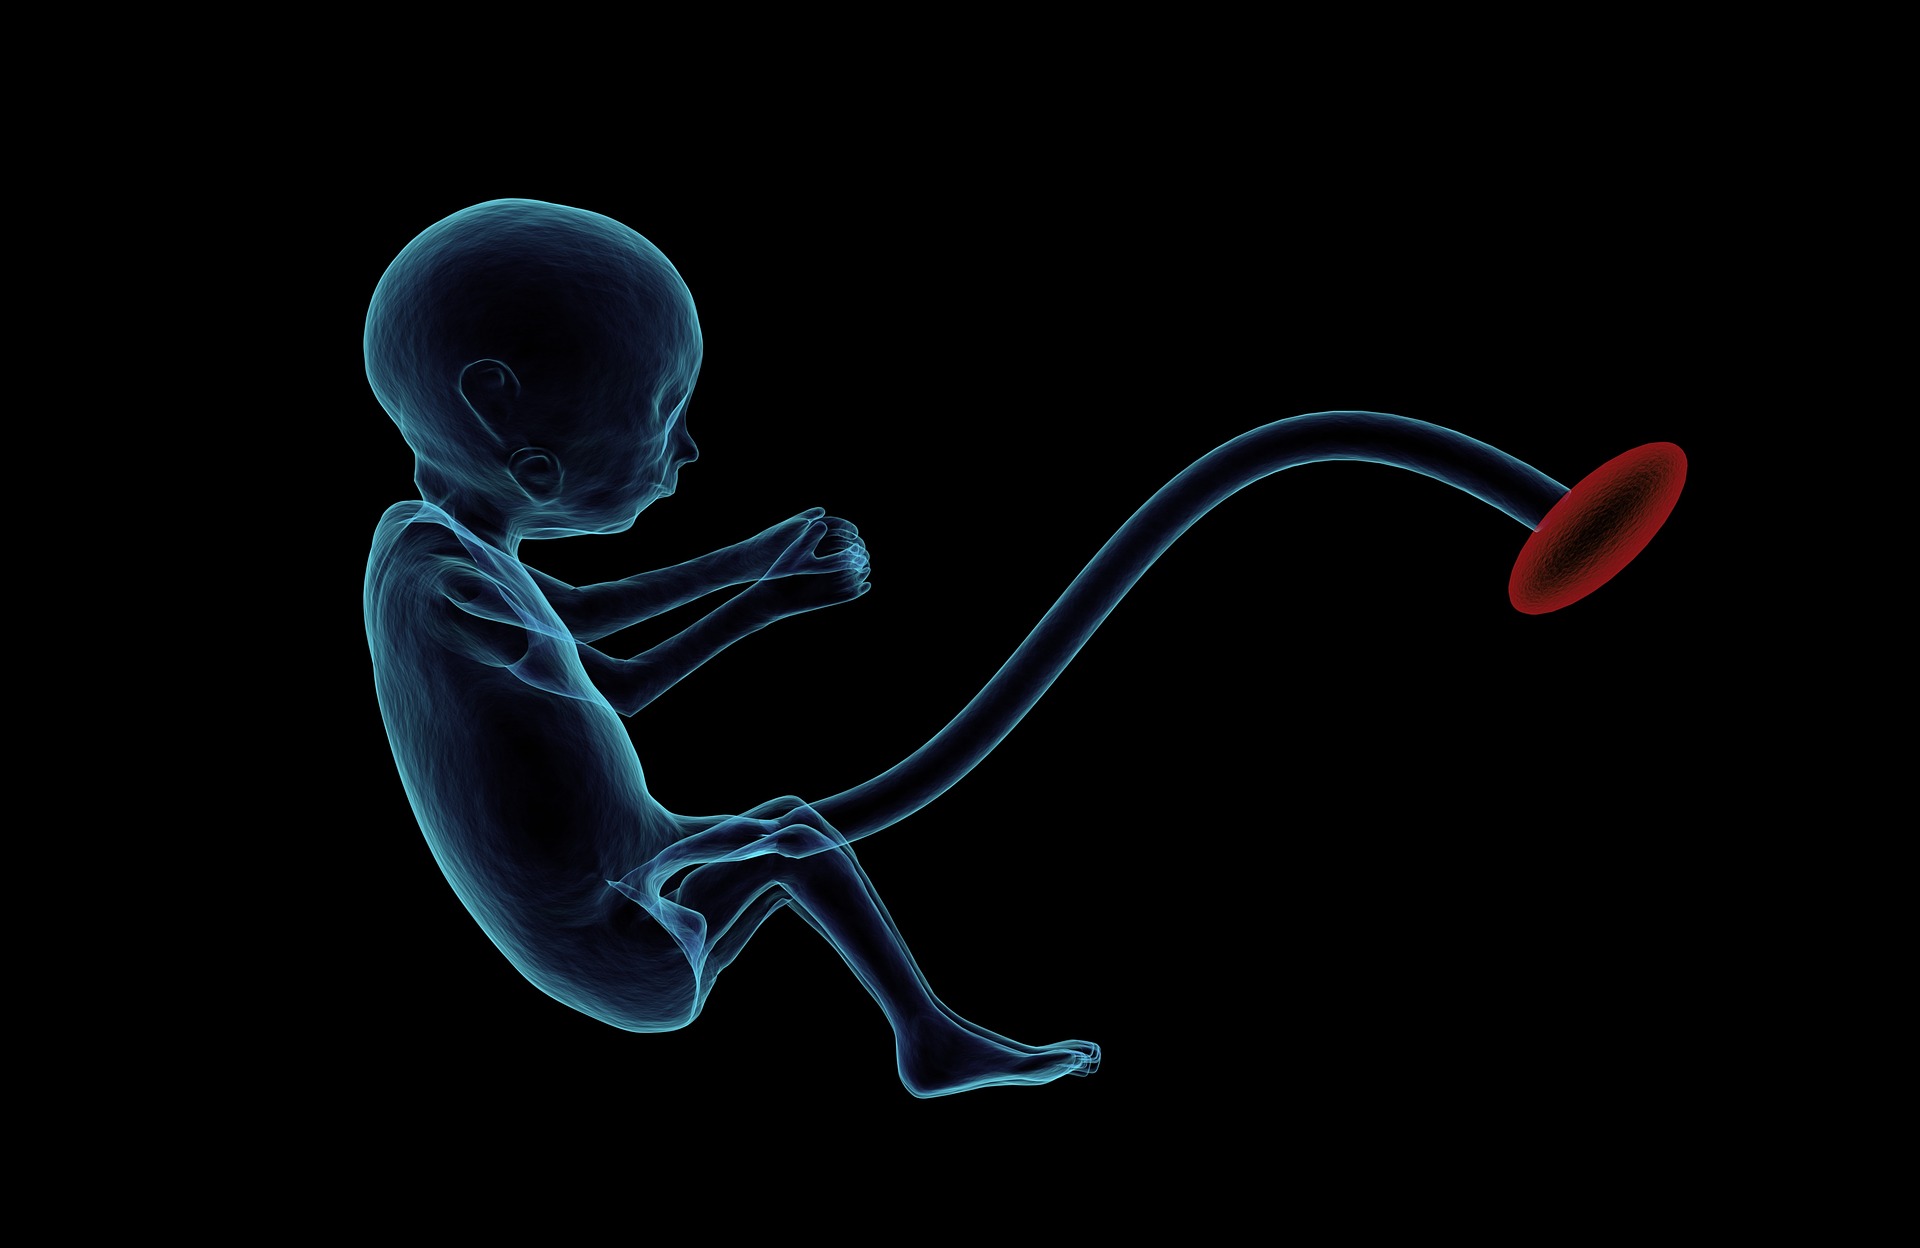

Pränataldiagnostik - ethisches Dilemma oder Wissen als Chance?

Mit einem positiven Schwangerschaftstest beginnt für die meisten Frauen ein medizinisches Untersuchungs- und Diagnosekarussell, aus dem sie kaum aussteigen können. Hauptmotiv vieler Schwangerer ist der Wunsch nach Sicherheit. So folgt eine diagnostische Untersuchung der nächsten. Ziel der Pränataldiagnostik ist es, Normabweichungen und Behinderung beim Fötus zu finden. Mit der Suche nach Auffälligkeiten ist meist Abtreibung verbunden.

Wir wollen an dieser Stelle einen differenzierten Blick auf das umstrittene Thema der Pränataldiagnostik werfen.